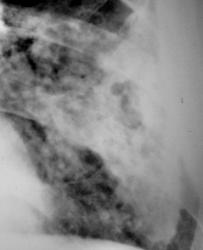

Иллюстрации 3, 4. Фрагменты рентгенограмм с увеличением. Структура затемнения неоднородная, ноздреватая. На боне интенсивного затемнения визуализируются округлые участки просветления. Местами определяются более интенсивные участки затемнения известковой плотности в виде «очаговости».